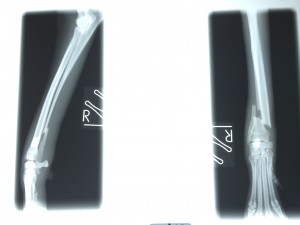

でもこれにも先生から説明があり『今回の手術はギブス固定ではなく、プレート2枚を使いしっかり固定をしているのでギブスは必要ありません。ギブスをしてしまうと、血流が悪くなること、自宅で患部の状況が解らないこと、骨折した足をほとんど使わないケースがあり筋肉が弱くなることもあるので必要なけでば使用しません』

そして詳しい手術経過の説明をして下さいました。今回の骨折は関節に近い部分であった為、より固定を安定させる為にプレートを2枚にしました。レントゲン写真を見ながら説明をして下さいました。(もちろん写真撮影は先生に許可を頂いてから行っています)

レントゲン写真を観た時は本当に可哀想になりました。。。痛かったね。。。